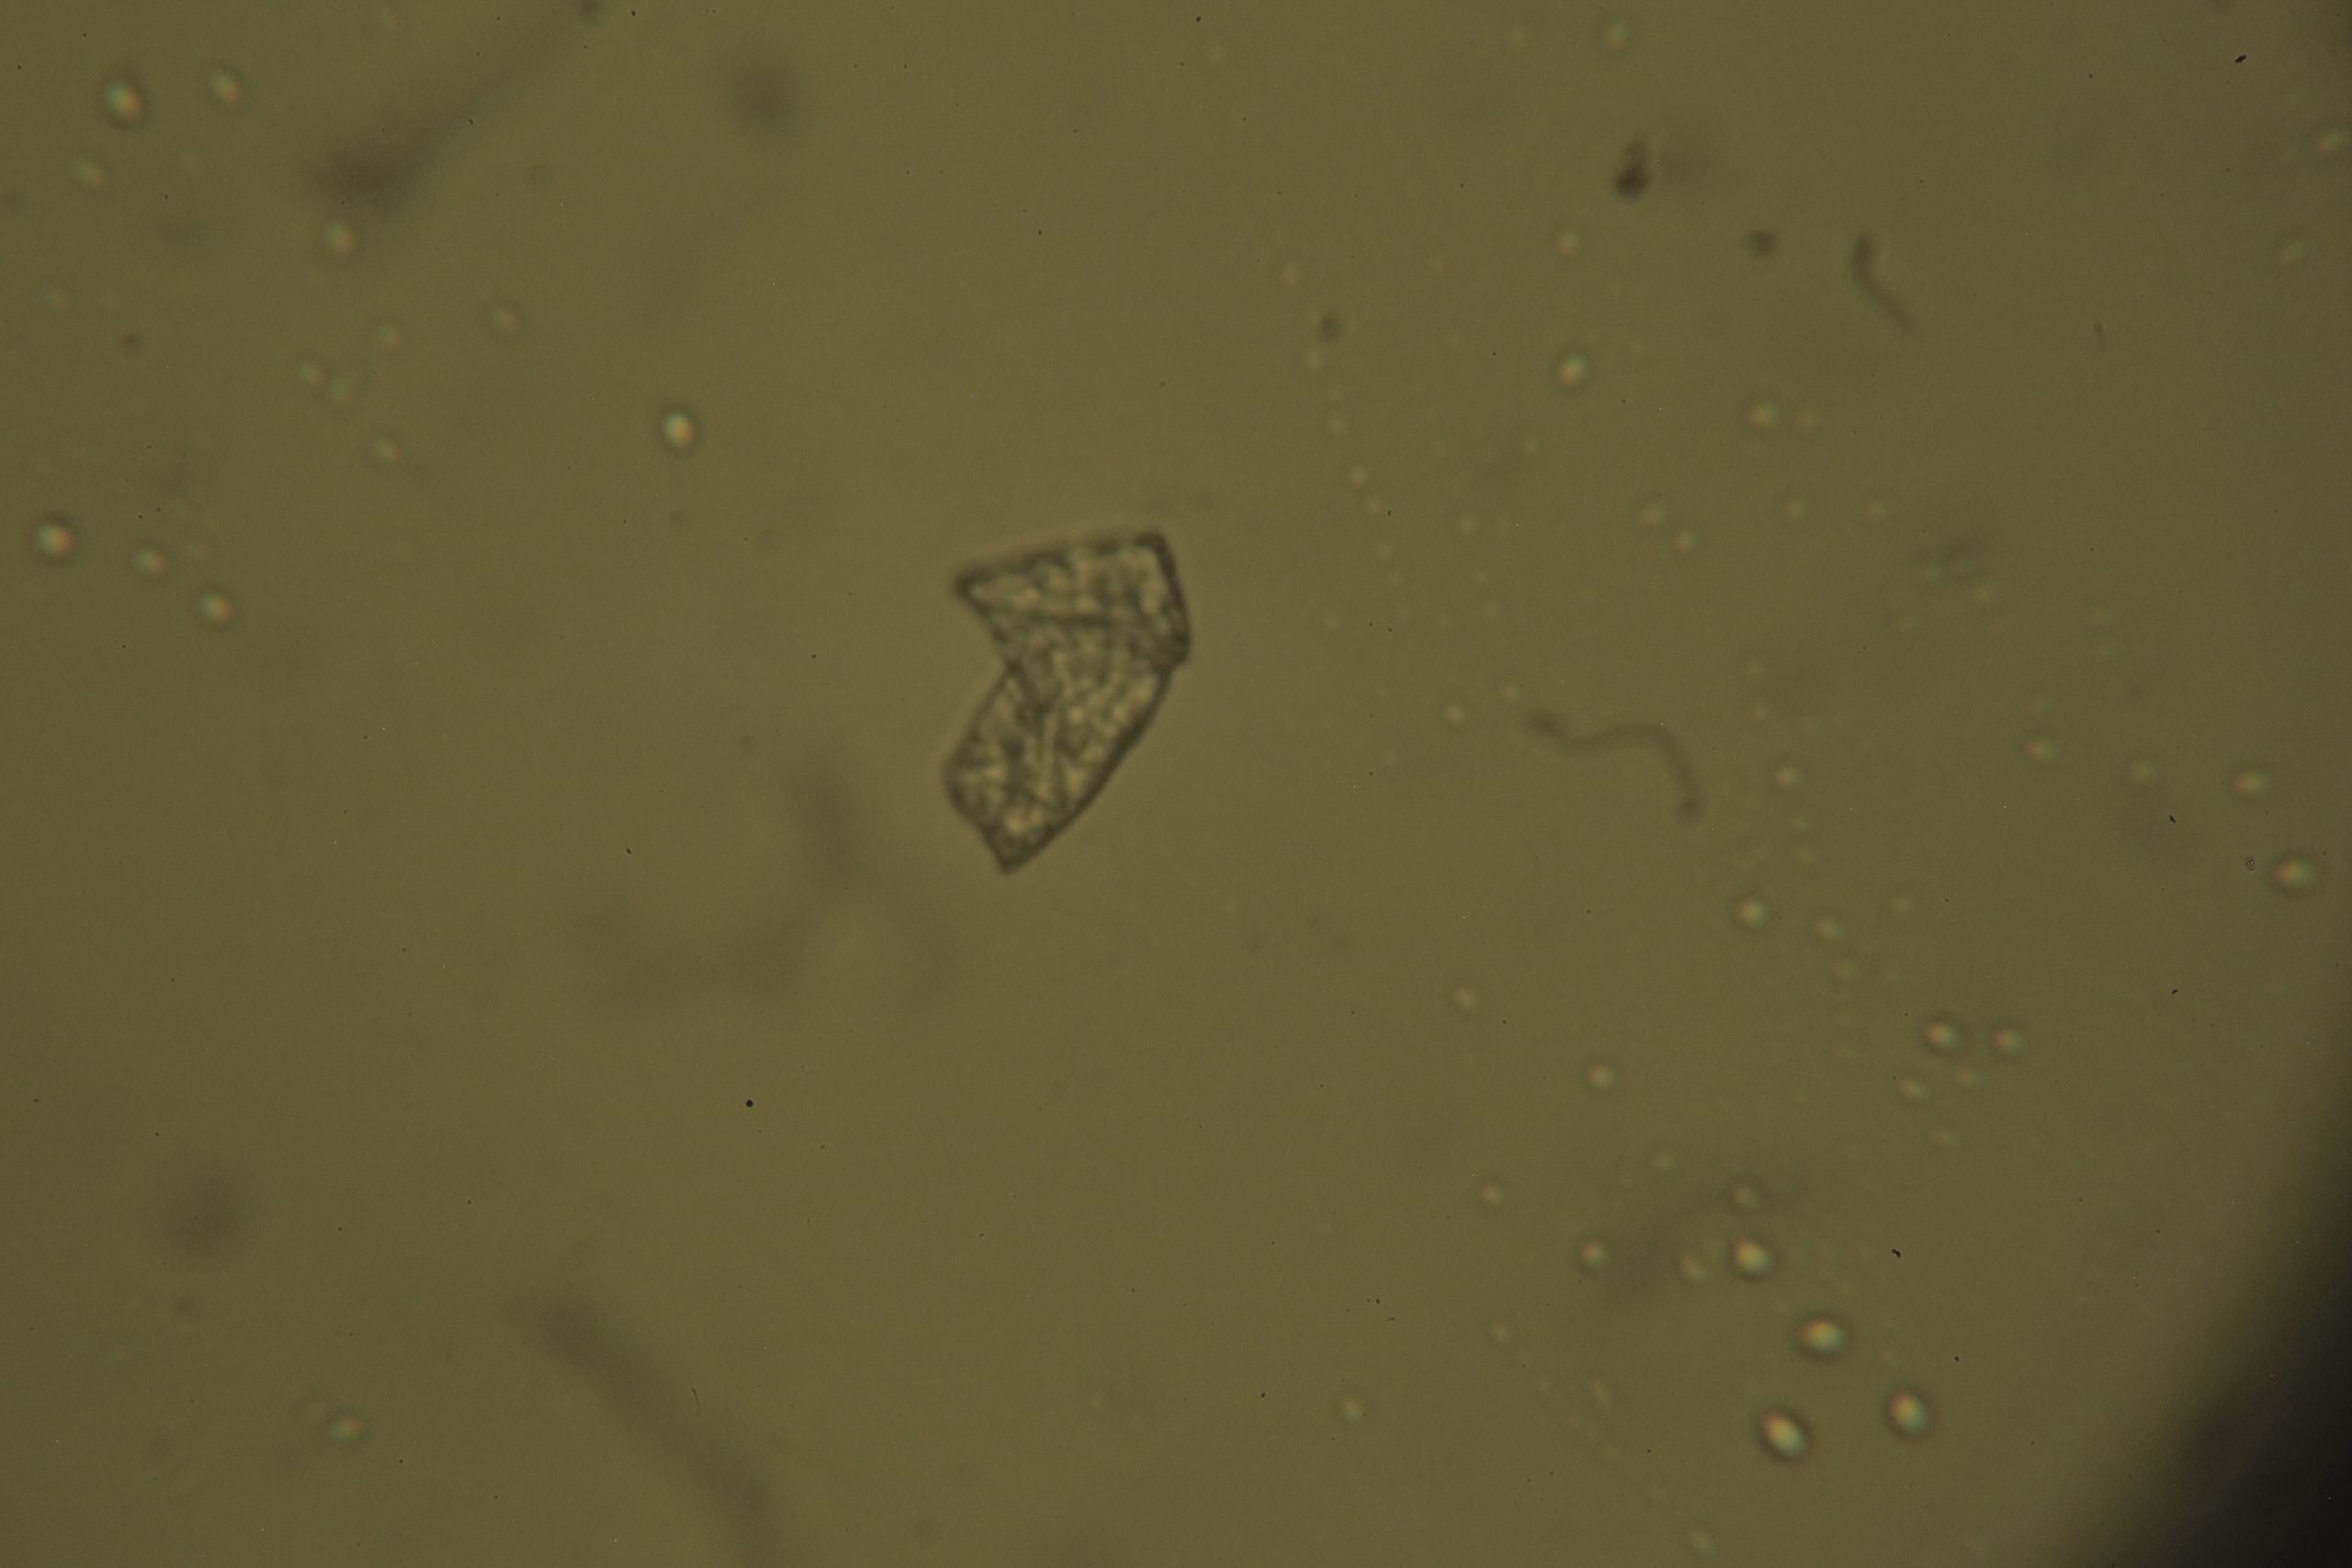

File:2018 12 18 0081.JPG

Original file(4,080 × 2,720 pixels, file size: 2.6 MB, MIME type: image/jpeg)